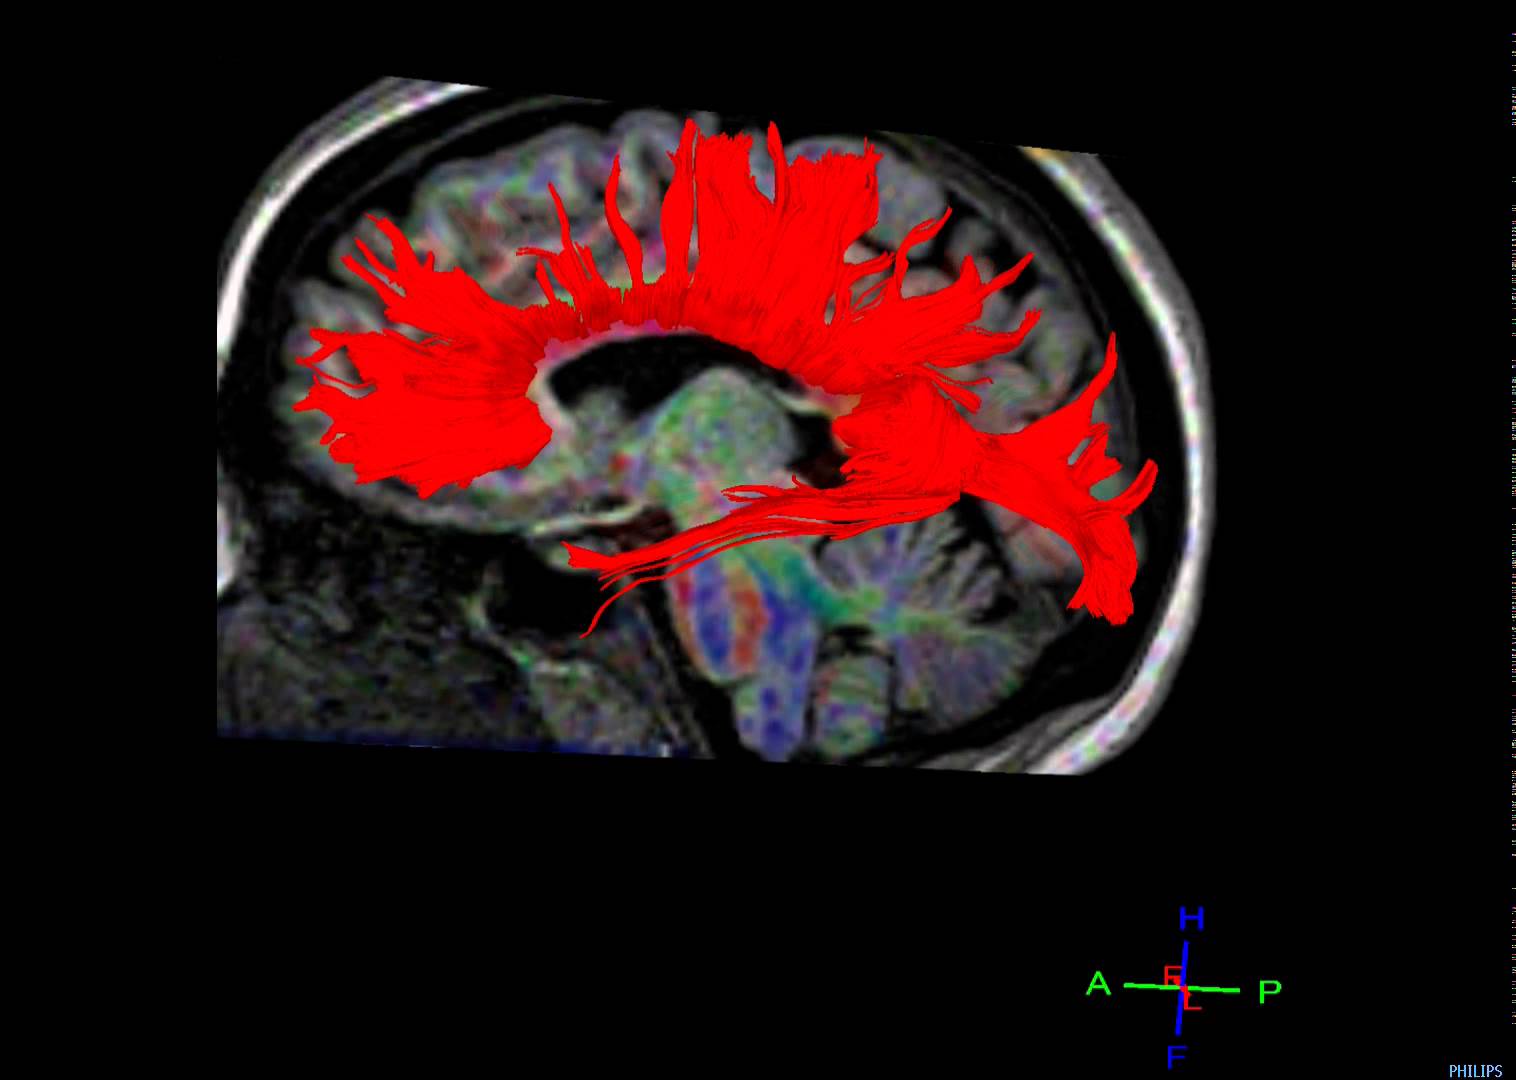

Dick Swaab zou er waarschijnlijk goed aan doen twee maal per dag twintig minuten te mediteren. Waarom? Ten eerste, omdat hij met de publiciteit die hij zoekt, meer mensen voor het hoofd lijkt te stoten dan er gelukkig mee lijkt te maken. En dat kan hem zelf toch ook niet echt gelukkig maken? In het NRC-artikel schrijft hij overigens niet te reageren op de talloze boze brieven die hij krijgt, maar ze wel in een grote lade te bewaren om er later misschien nog eens iets mee te doen. Ten tweede, en gezien vanuit Swaabs eigen wetenschappelijke visie op ‘het stoffelijke’ belangrijker nog: omdat alzheimer op oudere leeftijd regelmatig in verband wordt gebracht met het afnemen van de massa van de brug tussen onze linker- en rechterhersenhelft, genaamd corpus callosum (zie link naar Engelstalige abstract).. En laat mediteren nu net een aantoonbaar positief effect hebben op de massa van ons corpus callosum! (zie link naar Engelstalige abstract)Van oerbubbel tot inzicht

Mediteren leidt tot de verwerking van oerbubbels doordat we tijdens het mediteren niet bezig zijn met de interactie met onze omgeving, waardoor de hersenen, stationair draaiende, met zichzelf in overleg gaan. Dat is het stemmetje in ons hoofd. De rechterhersenhelft praat met de linker hersenhelft. De holist in ons praat met de analyticus. Het wordt niet gauw stil in ons hoofd, maar als we wat langer mediteren wordt de interne communicatie wel steeds rustiger en raken onze verschillende stemmetjes wel veel beter afgestemd. Op die manier hebben wij door te mediteren steeds minder innerlijke conflicten en ontwikkelen we op geïntegreerde wijze, naast aandacht voor de details ook een gezonde helikopterview op ons leven. Hierdoor kunnen onze gewone ervaringen, maar ook onze trauma’s, gemakkelijker een plaats krijgen in ons levensverhaal. Door de dagelijkse meditatie is er dus tijd voor de noodzakelijke interne communicatie die via de brug tussen links en rechts verloopt. Door het intensieve regelmatige gebruik van de brug wordt deze steviger en gaat hij bovendien langer mee. Zoiets zou ik, getrouwd zijnde met een wetenschapper, natuurlijk niet durven te beweren als er niet ook een degelijke studie was gepubliceerd die aantoont dat mediteren dementie bij ouderen lijkt te verminderen. (zie link naar Engelstalige abstract)ZenActueel home